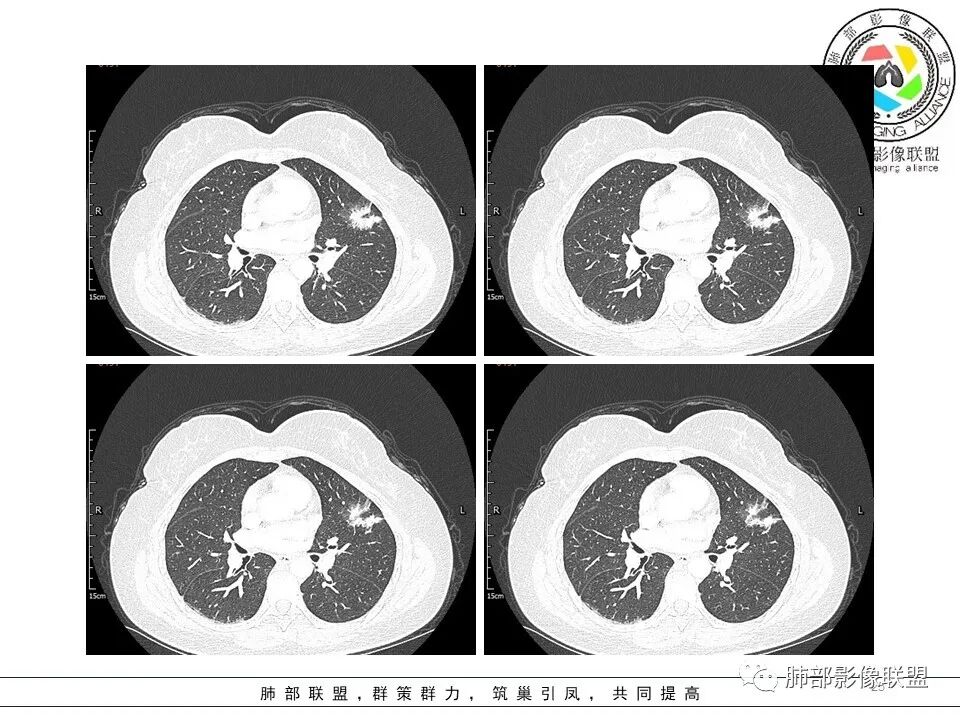

左肺上叶ggo,短毛刺,空泡征,6个月后复查病灶似变大,有轻度不均质强化,腺癌?胸膜下粟粒结节,无变化,良性?

分叶结节,内部结构杂乱,边缘板刷样毛刺,GGO边界清楚

胸膜牵拉

月牙铲?

常规要考虑腺癌

左肺上叶胸膜下不规则结节影,分叶、粗短毛刺,胸膜牵拉等,像个“刺头”。

未见钙化,也未显示液化坏死或空洞。

与支气管相关,但取层未能显示支气管进入情况。

1.病灶周围向几个方向膨出的边界清楚的磨玻璃影,这些磨玻璃影时隔几个月依然,几乎可以排除出血及一般的炎性改变。

2.病灶的胸膜牵拉线与其间病灶胸膜侧的磨玻璃边构成朝向胸壁的“月牙铲”结构,这种影像学表现某种程度上反映出病理学特征——病灶收缩+小叶间隔阻挡。

3.病灶实性密度区强化明显,这有助于我们区分一些其他类似病灶,如结核灶等!

4.邻近未见树芽征及卫星灶等。

结合临床,应当高度怀疑浸润性肺腺癌!

二.关于胸膜下小结节:

结节影太小,尚未能够充分反映出影像学特征。随访观察应当是恰当的处置方式。